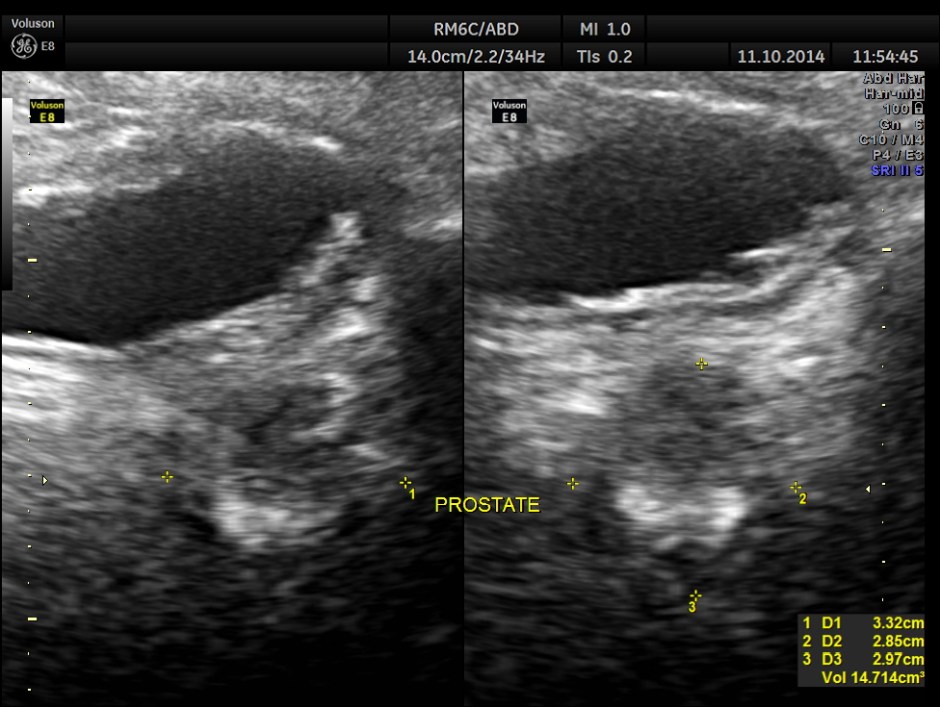

This was a 50 year old gentleman with history of occasional alcohol intake and complaints of tiredness and fatigue.

His ultrasound showed the following features.